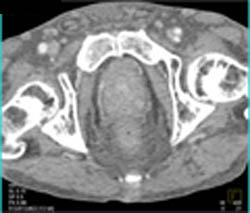

Diagnosis

Coronary Artery Stent